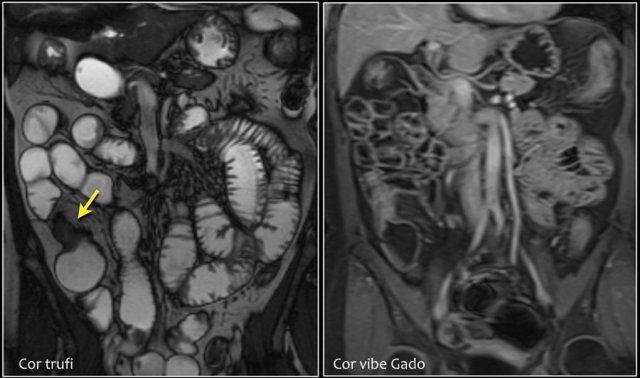

Chuỗi xung T1W sau tiêm thuốc tương phản từ có fat-sat (trái) và chuỗi xung T2W (phải) cho thấy một khối gây tắc nghẽn ở hỗng tràng với bờ dạng vai (mũi tên).

Có giãn ruột trước chỗ hẹp.

Các hình ảnh phía trên cho thấy một khối hình vòng ở đoạn gần hỗng tràng có tăng hấp thu FDG (mũi tên vàng).

Các hình ảnh MRI phía dưới cho thấy cùng khối hỗng tràng đó với bờ dạng vai và hạch to mạc treo (mũi tên đỏ), phù hợp với ung thư biểu mô tuyến.

Đây là ung thư biểu mô tuyến ở đoạn gần hỗng tràng.

Khối u được hiển thị rõ hơn trên MRI so với CT.